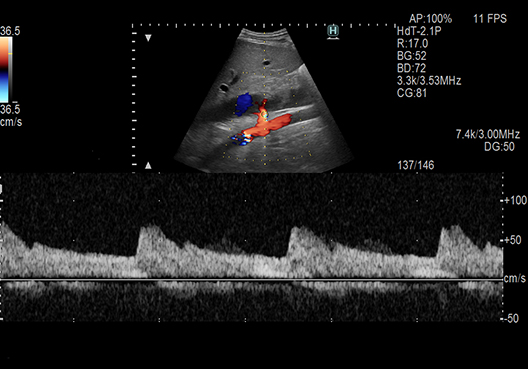

Settings like the position of Color ROI and cursor can be set by a single click operation in Doppler examination of a vessel. Convex transducers are supported as well. Additionally, it is possible to measure the Intima-Media Thickness (IMT) automatically by AutoIMT.

eTRACKING*1

Wave Intensity (WI)*1

The functions to support more detailed evaluation of hemodynamics are supported.